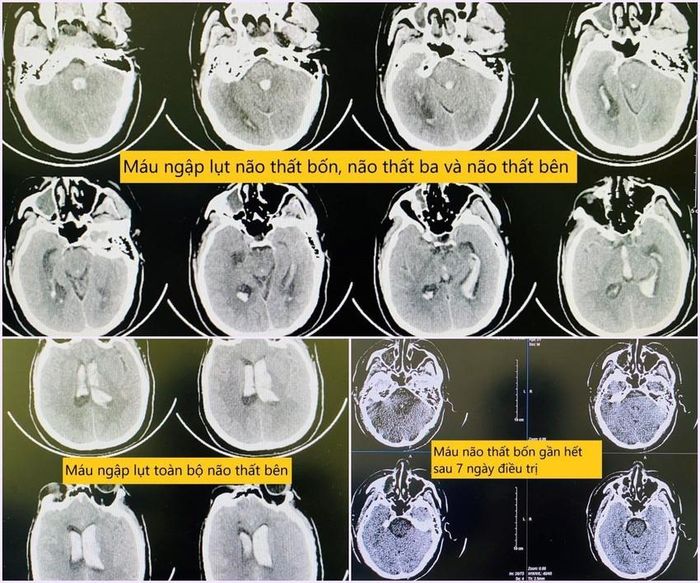

Hình ảnh chụp phim sọ não khi bệnh nhân nhập viện và sau quá trình điều trị.

“Kết quả về cho thấy hình ảnh chảy máu khủng khiếp, "ngập lụt" toàn bộ não thất bên, não thất ba, não thất tư, gây giãn não thất cấp, gây tắc nghẽn lưu thông hệ thống não thất. Với mức độ tổn thương như này nếu không can thiệp gần như chắc chắn tử vong”- bác sĩ Trung tâm Đột quỵ thông tin.